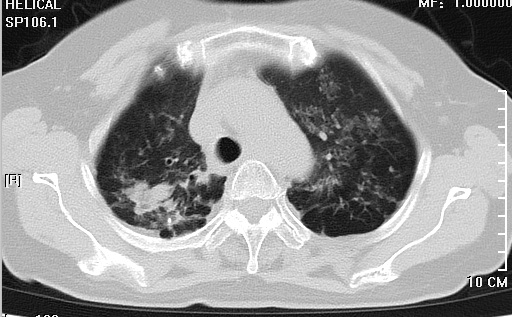

看到这样的胸部CT结果,神经外科医师做的第一件事就是再次核查患者流行病学史,反复确认新冠肺炎检查报告均为阴性后再请呼吸科、感染科医师会诊,会诊结合患者胸部CT均有考虑粟粒状肺结核灶可能,但患者入院后血常规、生化、血沉、痰找抗酸杆菌检查正常,结核分支核酸检测弱阳性。

由于患者颅内占位有手术需求,肺部问题诊断又不是非常明确,我科请院麻醉科、呼吸内科、感染科、重症医学科及我院弋矶山总院神经外科专家赵心同博士就患者肺部问题、手术以及术后相关问题展开多学科会诊及讨论。

会诊中,各科主任认真阅片并分析交流,在管床医师汇报完患者相关病史后,各个学科主任相继就本科专业导向做出发言,就患者是非需要术前抗结核治疗、肺部情况是否耐受手术等做出讨论,讨论中调阅2年前患者既往我院就诊的肺部影像资料,对比本次胸部CT无明显变化,最终讨论决定积极手术治疗并做好应急预案。